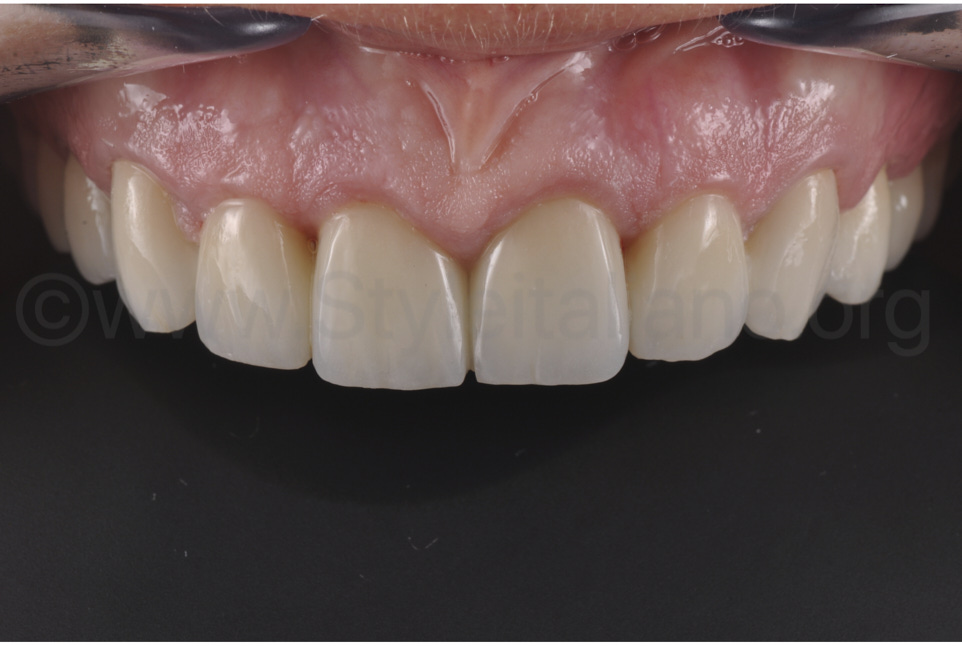

Фото 9.

За три місяці після цього, завдяки дуже простим процедурам полірування, оптичним властивостям матеріалу та його стабільності, текстура поверхні виглядає дуже задовільно. До того ж, таке зручне, просте та швидке полірування попереджає формування біоплівки й нальоту. Через недостатній об’єм ясен, обидва бічні різці є занадто великими у пришийковій зоні, щоб це компенсувати. Але цей недолік буде виправлено під час встановлення керамічної реставрації.

Фото 13.

Одразу після завершення операції можна було помітити ефект збільшення об’єму ясен внаслідок введення сполучнотканинного трансплантата, що значною мірою покращило зовнішній вигляд. Отже, можна відразу створювати ідеальну бажану форму зубів, заплановану на wax-up, а потім клінічну ситуацію адаптувати до неї. Повторимо, загоєння ясен залежатиме від форми зубів. Тому ми вважаємо, що проведення пластичної операції одночасно зі встановленням кінцевої реставрації позитивно впливає на кінцевий результат лікування.